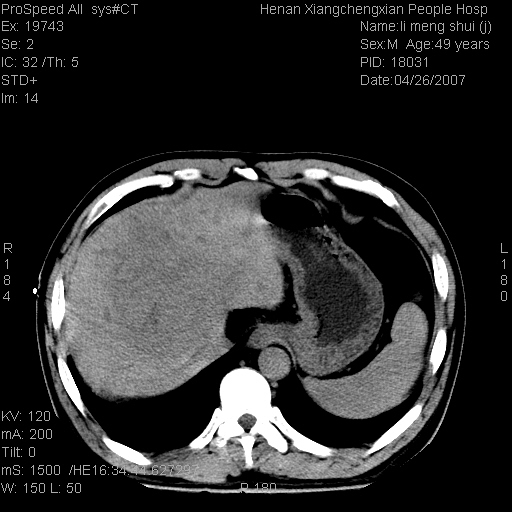

| 患者,男,49岁, 腹疼伴恶心\\呕吐20天,20天前无明显诱因出现右上腹部疼痛,钝疼,无放射,伴恶心\\呕吐,不伴发热.患者不愿增强. b超:肝脏右叶实性占位. ct:肝脏右叶可见一巨块状圆形低密度影,大小约93mm*84mm,其内可见点状高密度影,胆囊、胰腺、脾脏大小、形态及密度未见异常,腹膜后间隙未见肿大淋巴结影。 印象:肝脏右叶巨大肿块,性质待定,建议增强并穿刺活检进一步确诊。 ct平扫: ![]() ![]() ![]() ![]() ![]() ![]() ![]() ![]() ![]() ![]() ![]() ![]() ![]() ![]() ![]() ![]() ![]() 肝脏右叶肿块ct引导下穿刺活检术 患者于16时05分仰卧于ct检查台上,首先行肝脏ct扫描确定进针位置、深度、角度。在局麻下行ct引导下肝脏右叶肿块穿刺活检术。常规消毒、铺巾、局麻。在ct引导下使活检针经右侧腋中线、第9肋间隙垂直胸壁进针90mm,针头进入病变预定位置。在病变预定位置多点、多方向抽取小米样病变组织多块,涂片五张送病理检查。术后穿刺点局部无出血,未出现腹腔积液等并发症。术中及术后患者生命体征稳定,手术于17时10分成功完成。患者安返病房。 穿刺片 ![]() ![]() ![]() ![]() ![]() ![]() ![]() ![]() ![]() ![]() ![]() ![]() ![]() ![]() ![]() ![]() 病理结果肝细胞癌 ![]() 原贴地址:http://www.radinet.com.cn/forum_view.asp?forum_id=4&view_id=24130 ok |